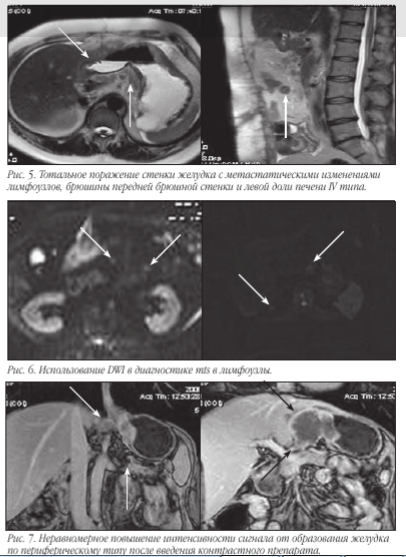

Постконтрастные томограммы

После введения контрастного препарата «Магневист» определяется неравномерное повышение интенсивности сигнала от образования желудка по периферическому типу.

Визуализируется поражение не только брюшного отдела пищевода, но и дистальной трети его грудной части с признаками стеноза.